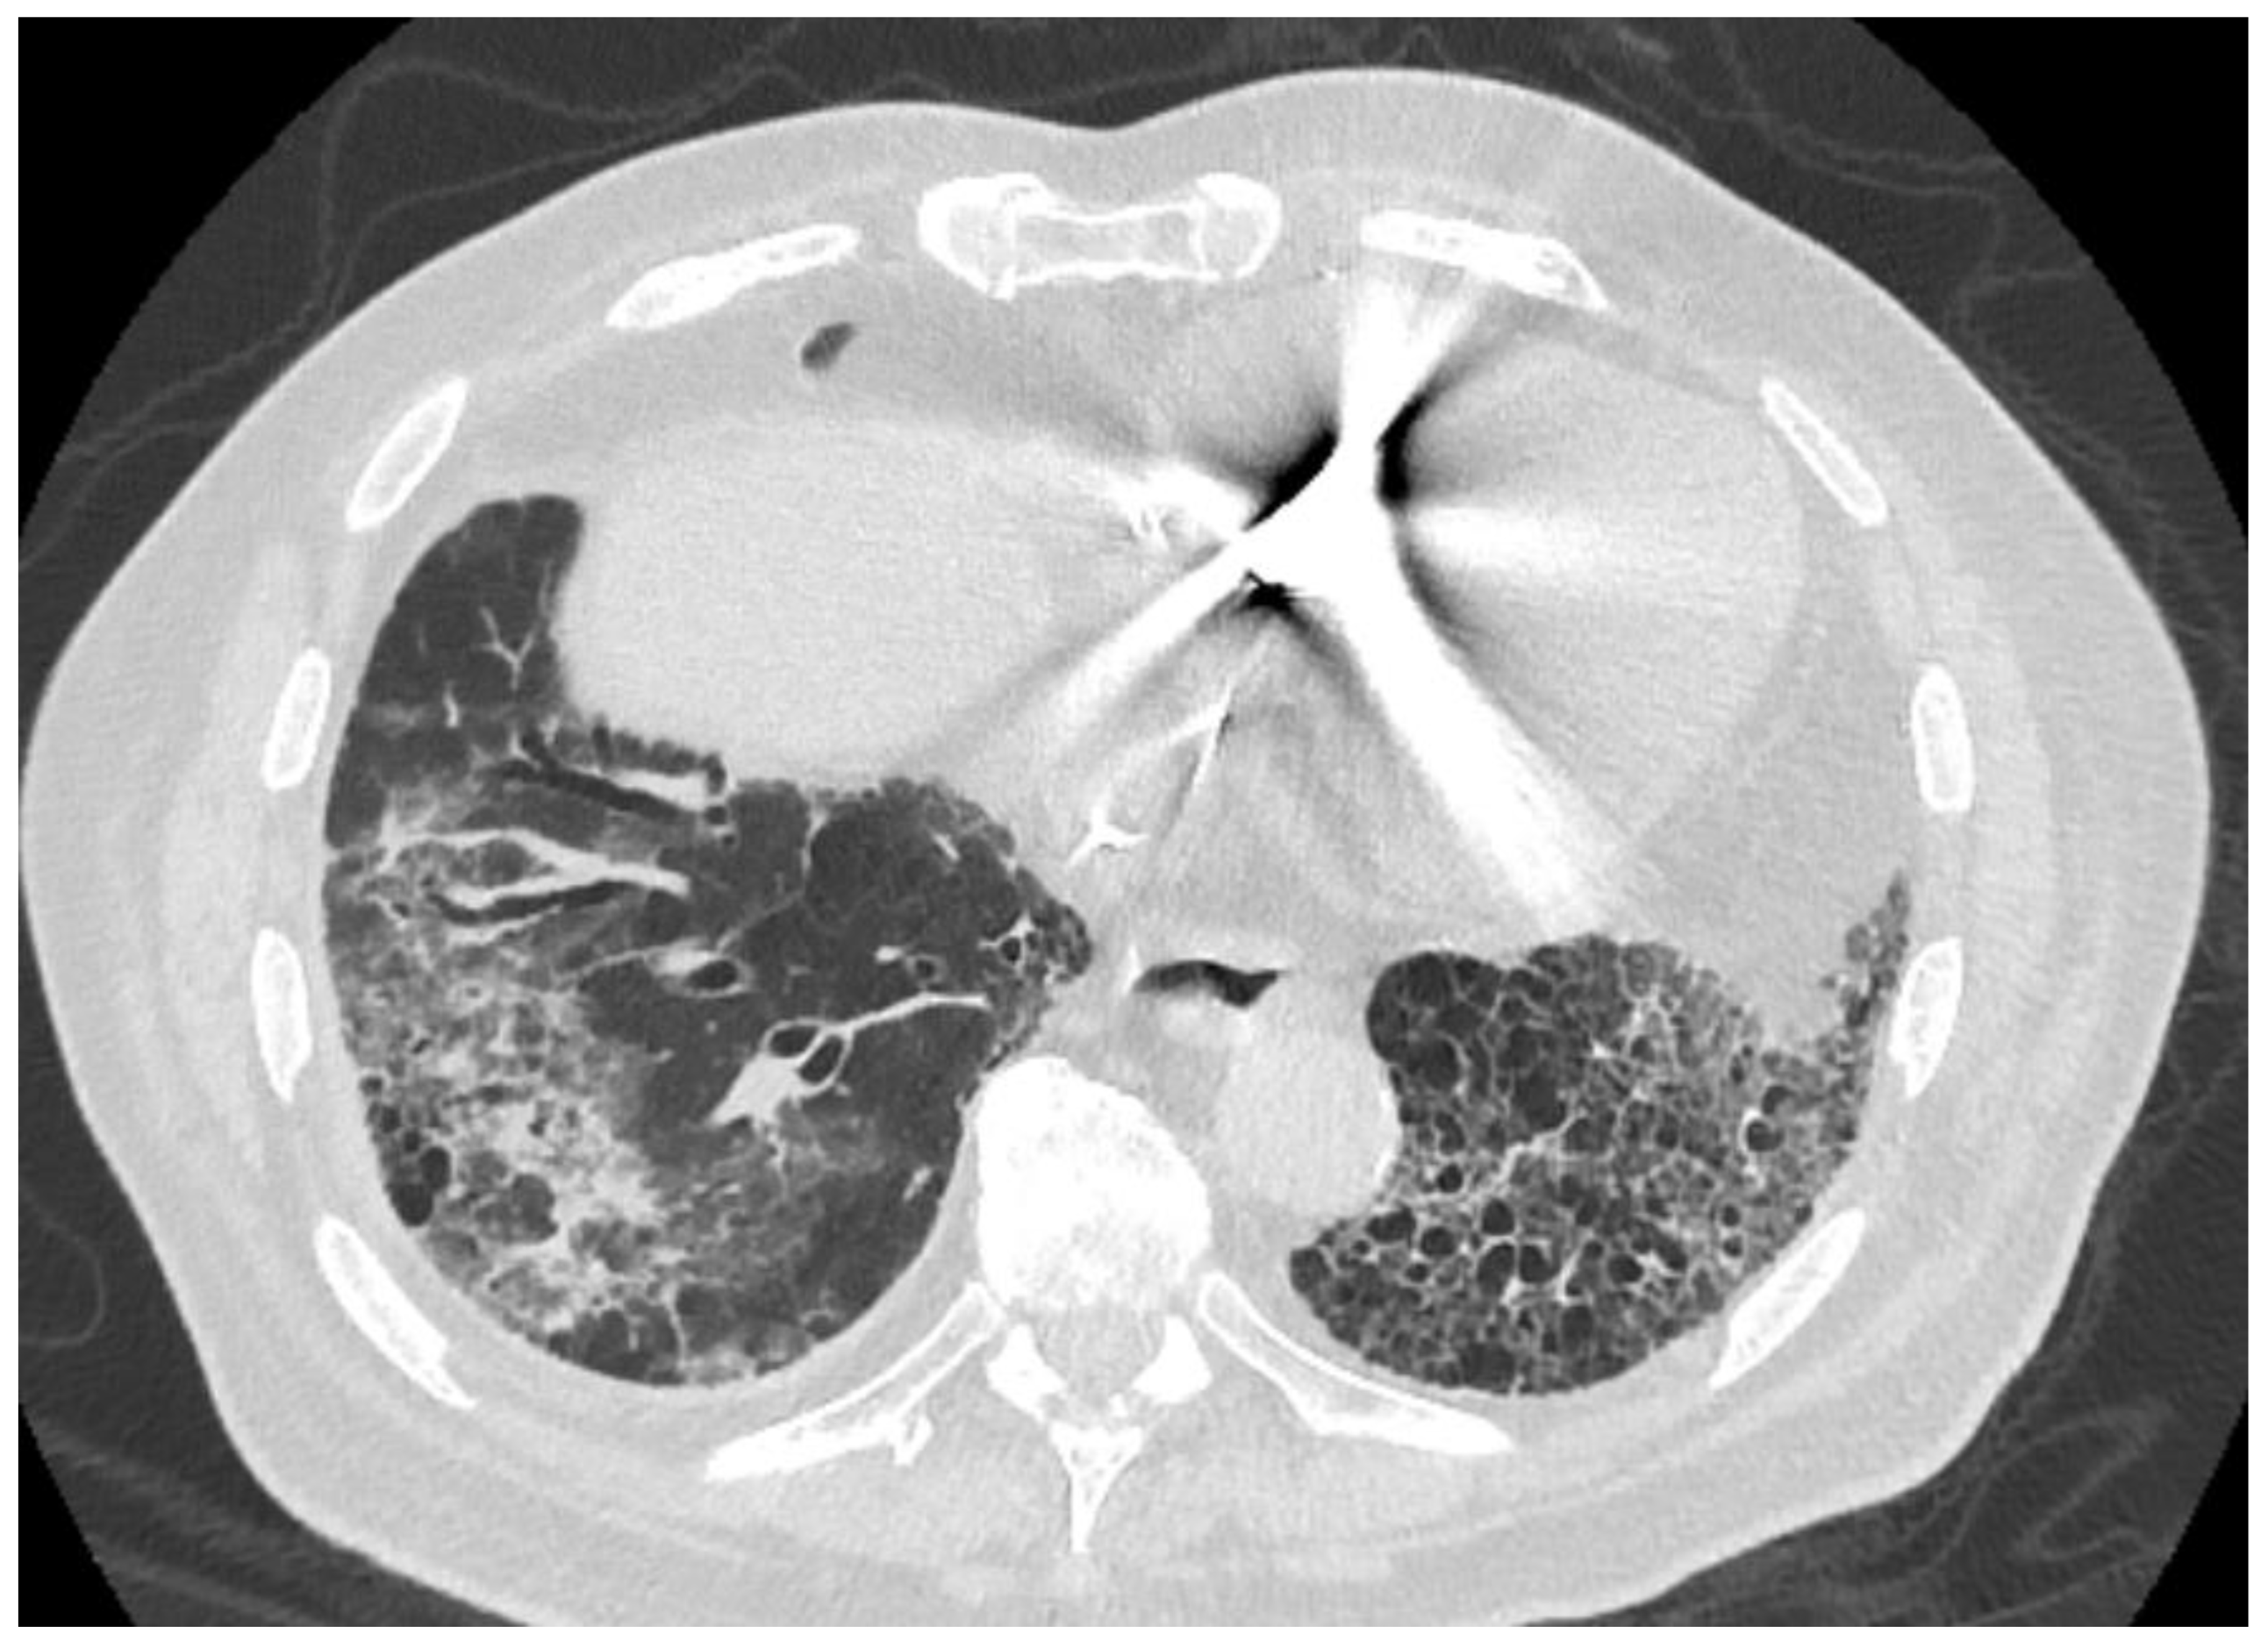

2. Case Presentation